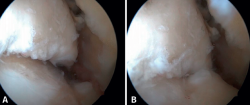

El PAT se define como dolor y/o limitación del rango de movilidad que aparece con la dorsiflexión del tobillo, debido a la presencia de tejidos blandos u óseos que se interponen entre las superficies articulares. Se distingue entre un pinzamiento de partes blandas (proliferación sinovial, engrosamiento del ligamento de Bassett, adherencias capsulares), óseo (osteofitos o alteraciones en el eje del retropié o tobillo) (Figura 1) o mixto (Tabla 1). El PAT se puede subdividir en pinzamiento central, anterolateral y anteromedial(8), siendo los dos primeros los más frecuentes(9). El PAT anterolateral suele ser de partes blandas, mientras que el anteromedial suele producirse por conflicto de espacio entre osteofitos del cuello talar y anteriores al maléolo medial en dorsiflexión(9,10). El PAT es la causa más común de dolor en la parte anterior del tobillo que empeora con la dorsiflexión. No obstante, el pinzamiento posterior puede ser más frecuente en ciertos grupos de pacientes, como bailarines o futbolistas, debido a la repetición de movimientos en flexión plantar forzada(4).

Figura 1. Pinzamiento óseo entre astrágalo y tibia. A: tobillo en flexión plantar; B: tobillo en dorsiflexión mostrando el choque entre ambos osteofitos.